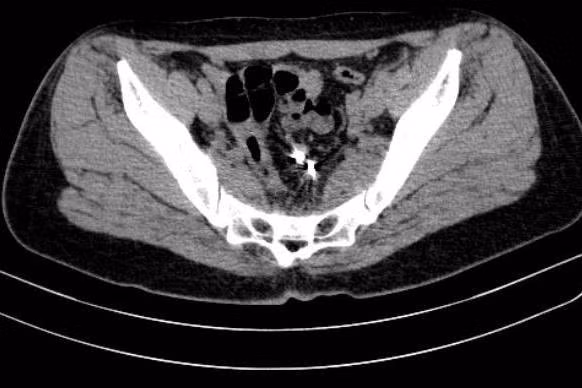

Vietnamnet đưa tin về trường hợp này cho biết, trước khi vào viện, chị L. bị đau bụng vùng chậu dưới rốn âm ỉ, kèm đi ngoài ra máu. Trong suốt 3 năm đặt vòng tránh thai chị không đi kiểm tra lại.

Sau khi có kết quả xét nghiệm, chiếu chụp, các bác sĩ Khoa Phẫu Thuật Tiêu hóa - Gan mật tụy, Bệnh viện Bạch Mai (Hà Nội), quyết định phẫu thuật để lấy vòng tránh thai lạc chỗ và xử lý chỗ thủng đại tràng cho người phụ nữ này. Bệnh nhân được xuất viện sau 6 ngày.

| Hình ảnh vòng tránh thai trong đại tràng. Ảnh: BVCC/Vietnamnet. |